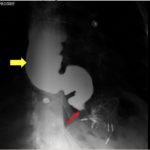

The chest X-ray demonstrated a markedly widened mediastinum (red brackets), raising concern for thoracic aortic aneurysm/aortic dissection, which prompted labs and contrast-enhanced computed tomography (CT) of the chest. The CT revealed a dilated proximal esophagus that narrowed distally (yellow tracing and red arrow), with particulate material, mass-effect on the trachea (purple outline), and bilateral patchy opacities suggesting aspiration. Barium esophagram showed a drastically dilated esophagus filled with contrast (yellow arrow), terminating into the classic “bird’s beak sign” (red arrow) at the lower esophageal sphincter (LES). Esophageal manometry later confirmed achalasia, proving that widened mediastina can have unexpected etiologies.

Achalasia is a rare (prevalence ~0.3-9.5/100,000, increasing with age) digestive disorder characterized by denervation to the distal esophagus, promoting regional aperistalsis and tonic contraction of the LES.1-3 Achalasia most commonly presents as acute, simultaneous dysphagia to both solids and liquids, but can present as heartburn, regurgitation, or even unexplained cough.1-3 A dilated esophagus with narrowing at the LES (“Bird’s Beak Sign”) and delayed esophageal emptying on barium esophagram are pathognomonic for achalasia (sensitivity 90%, specificity 95%),4 as is distal aperistalsis with increased resting LES tone on high-resolution manometry (sensitivity 98%, specificity 96%).5 Pharmacologic LES relaxation may be trialed, but surgical myotomy is usually necessary.1,2,3,6 Our patient underwent laparoscopic Heller myotomy resulting in a dilated, aperistaltic esophagus with no evidence of obstruction and is being followed for continued GERD and dysphagia.